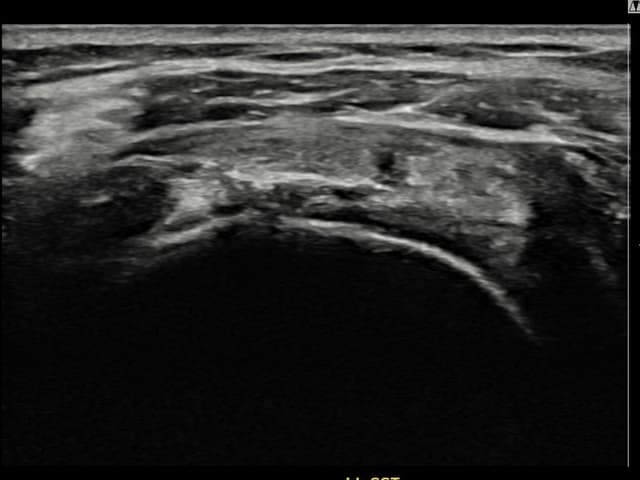

[経過期間: 23.07.31~23.09.27]

[縫縮術] 超音波検査にて左 棘上筋腱 부착부 광범위 部分断裂(13mm × 5mm (腱厚の約65%欠損))を確認。縫縮術施行後、腱の連続性が回復し、日常生活に復帰されました。